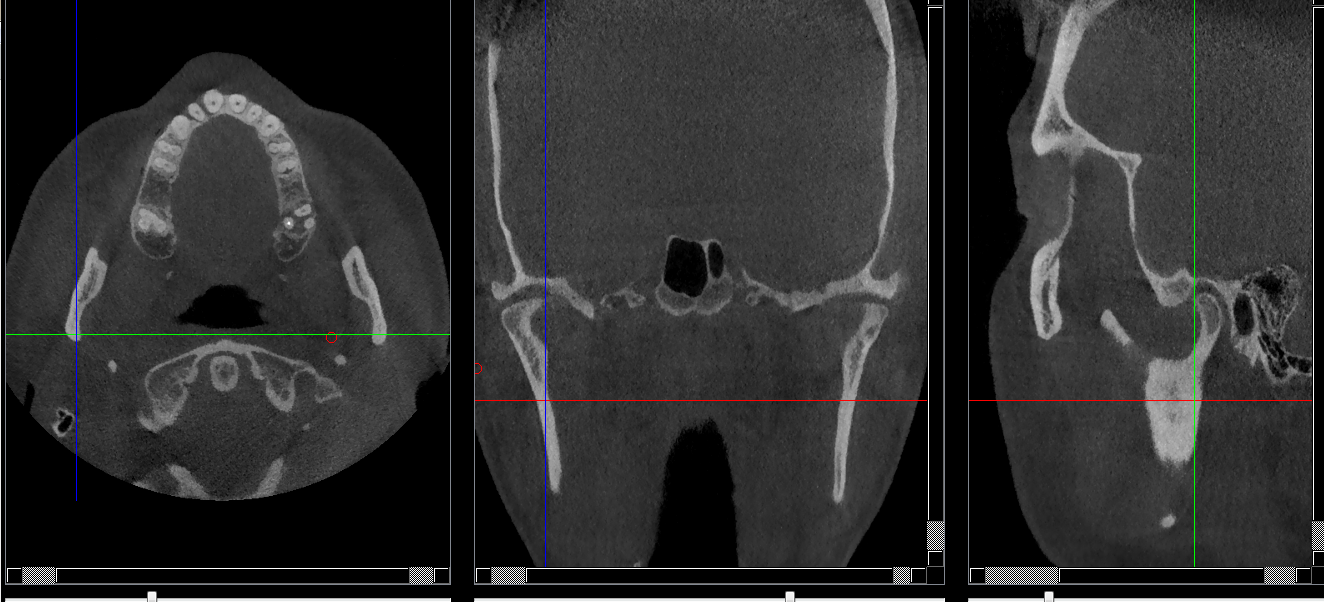

Structures osseuses

Ramus

Repères anatomiques

- Coupe transversale

- Début : Branche horizontale

- Fin : Condyle

- Coupe frontale

- Début : La lame criblée de l'éthmoide

- Coupe saggitale

- Début : Processus zygomatique

- Fin : La grande aile du sphénoide